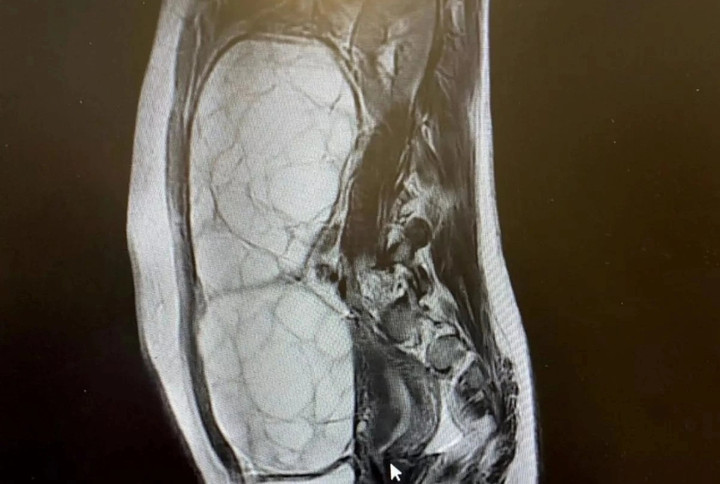

Alex lần đầu tiên nhận thấy các triệu chứng khó chịu trong một chuyến du lịch cùng gia đình và khi về nhà, cô đã nhanh chóng đặt lịch hẹn kiểm tra sức khỏe với bác sĩ. Cô được xét nghiệm máu và chỉ một tuần sau, được đưa đến bệnh viện để siêu âm. Vào thời điểm này, cô mất thị lực ngoại vi ở mắt trái và được thông báo rằng buồng trứng của cô đã phát triển thêm 13 cm.

Các xét nghiệm tiếp theo cho thấy Alex có khối u tuyến yên hiếm gặp, cả thế giới mới chỉ ghi nhận tổng cộng 20 trường hợp tương tự và cô chỉ cách cái chết một tuần. "Khi mới 16 tuổi, cuộc sống của tôi vụt qua trước mắt. Những gì tôi thực sự quan tâm, không còn ý nghĩa gì với tôi kể từ ngày đó", nữ sinh tiết lộ cô được chỉ định phải phẫu thuật gấp trước khi khối u vỡ ra và gây nguy hiểm đến tính mạng.